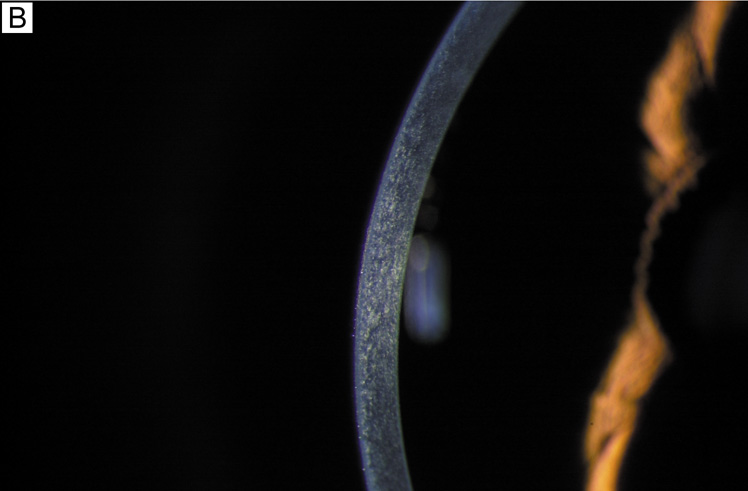

Although this review is primarily concerned with healthy, normal corneal endothelium, there are many exogenous stresses that could potentially damage the corneal endothelium. Perhaps the most common interventions that affect the cornea/endothelium include contact lens wear, excimer laser refractive surgery (LASIK, PRK), and intraocular surgery (cataract surgery, refractive IOL surgery, corneal transplantation). Contact lens wear does not appear to cause loss of endothelial cell density, but can acutely induce reversible corneal edema and/or can cause chronic signs of endothelial cell stress (increased polymegathism and decreased pleomorphism).58,114 Contact lens-induced endothelial cell changes are thought to occur because of hypoxia, as they are not observed with more oxygen permeable lenses.114 Excimer-based refractive surgery has only been found to induce acute, transient endothelial cell stress (increased polymegathism and decreased pleomorphism) and loss of barrier function if performed on a cornea with a residual corneal thickness ≤200 μm, presumably because of the shockwave produced by the laser ablation.85 Otherwise, no long-term effects have been linked to laser refractive surgery.85